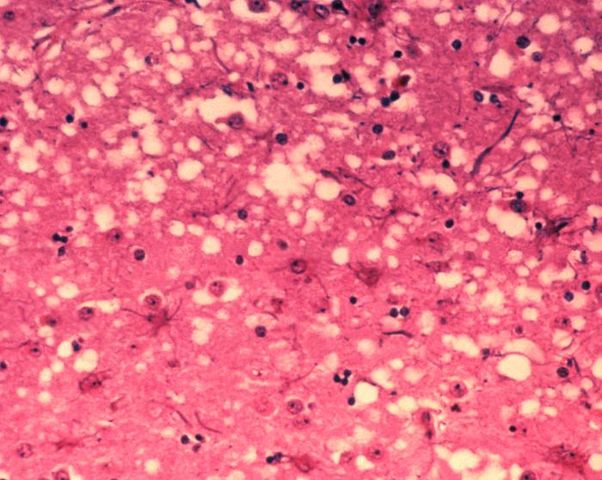

English: This micrograph of brain tissue reveals the cytoarchitectural histopathologic changes found in bovine spongiform encephalopathy. The presence of vacuoles, i.e. microscopic “holes” in the gray matter, gives the brain of BSE-affected cows a sponge-like appearance when tissue sections are examined in the lab.